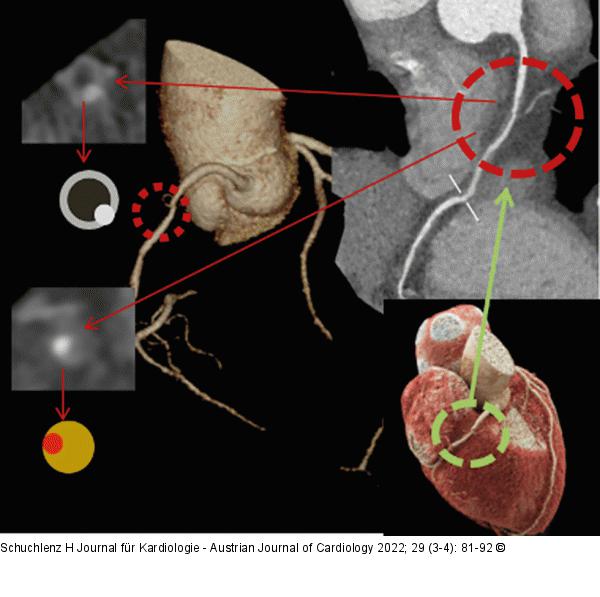

Abbildung 4: Plaque Hochrisikoplaque im Bereich der RCA, hohe Plaquelast, links oben NRS. RCA: Right Coronary Artery; NRS: Napkin Ring Sign |

Hochrisikoplaque im Bereich der RCA, hohe Plaquelast, links oben NRS. RCA: Right Coronary Artery; NRS: Napkin Ring Sign |